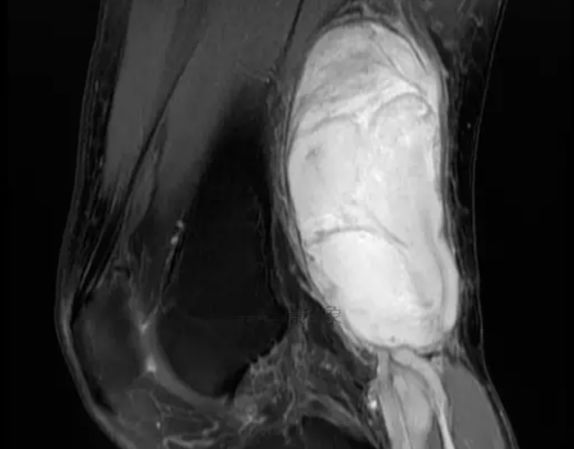

图片来源:华夏影像诊断中心

*当怀疑为软组织肉瘤时,要先完成MRI/CT、彩超等检查,然后进行活检(首选穿刺活检)获得组织学诊断,以便对软组织肉瘤进行分型和分期,制定下一步治疗方案。